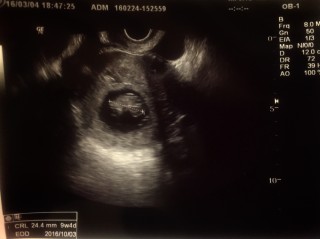

2日前からつわりが軽くなり心配していましたが、24.4mm、順調でした。

CRL24.25mm予定日はクリスマスです。 妊娠前から子宮筋腫が2つ。今回の検診でさらに数が増えて3、4個はあることが分かりました。 不安は尽きませんが赤ちゃんの生命力を信じるのみ!! 同じ不安を抱えたママの励みにもなりますように☆

第2子に会いに母子手帳を持って検診へ!2週間ぶりに会えました。前回よりも3倍も大きくなってくれていて、順調でした。予定日もこのまま行くと、クリスマスベビーに。2回流産が続いたので、このまま順調に育っていって欲しいです。

人の形になってて感動~!予定日も確定し一安心です。うっすらと目と口も見えるような笑

へその緒がハッキリ見えた。やったぁ。去年流産して1年後再び赤ちゃんがお腹に戻ってきてくれました。まだまだ不安な事がいっぱいあると思うけど… 頑張って大きくなってね。祈っています。